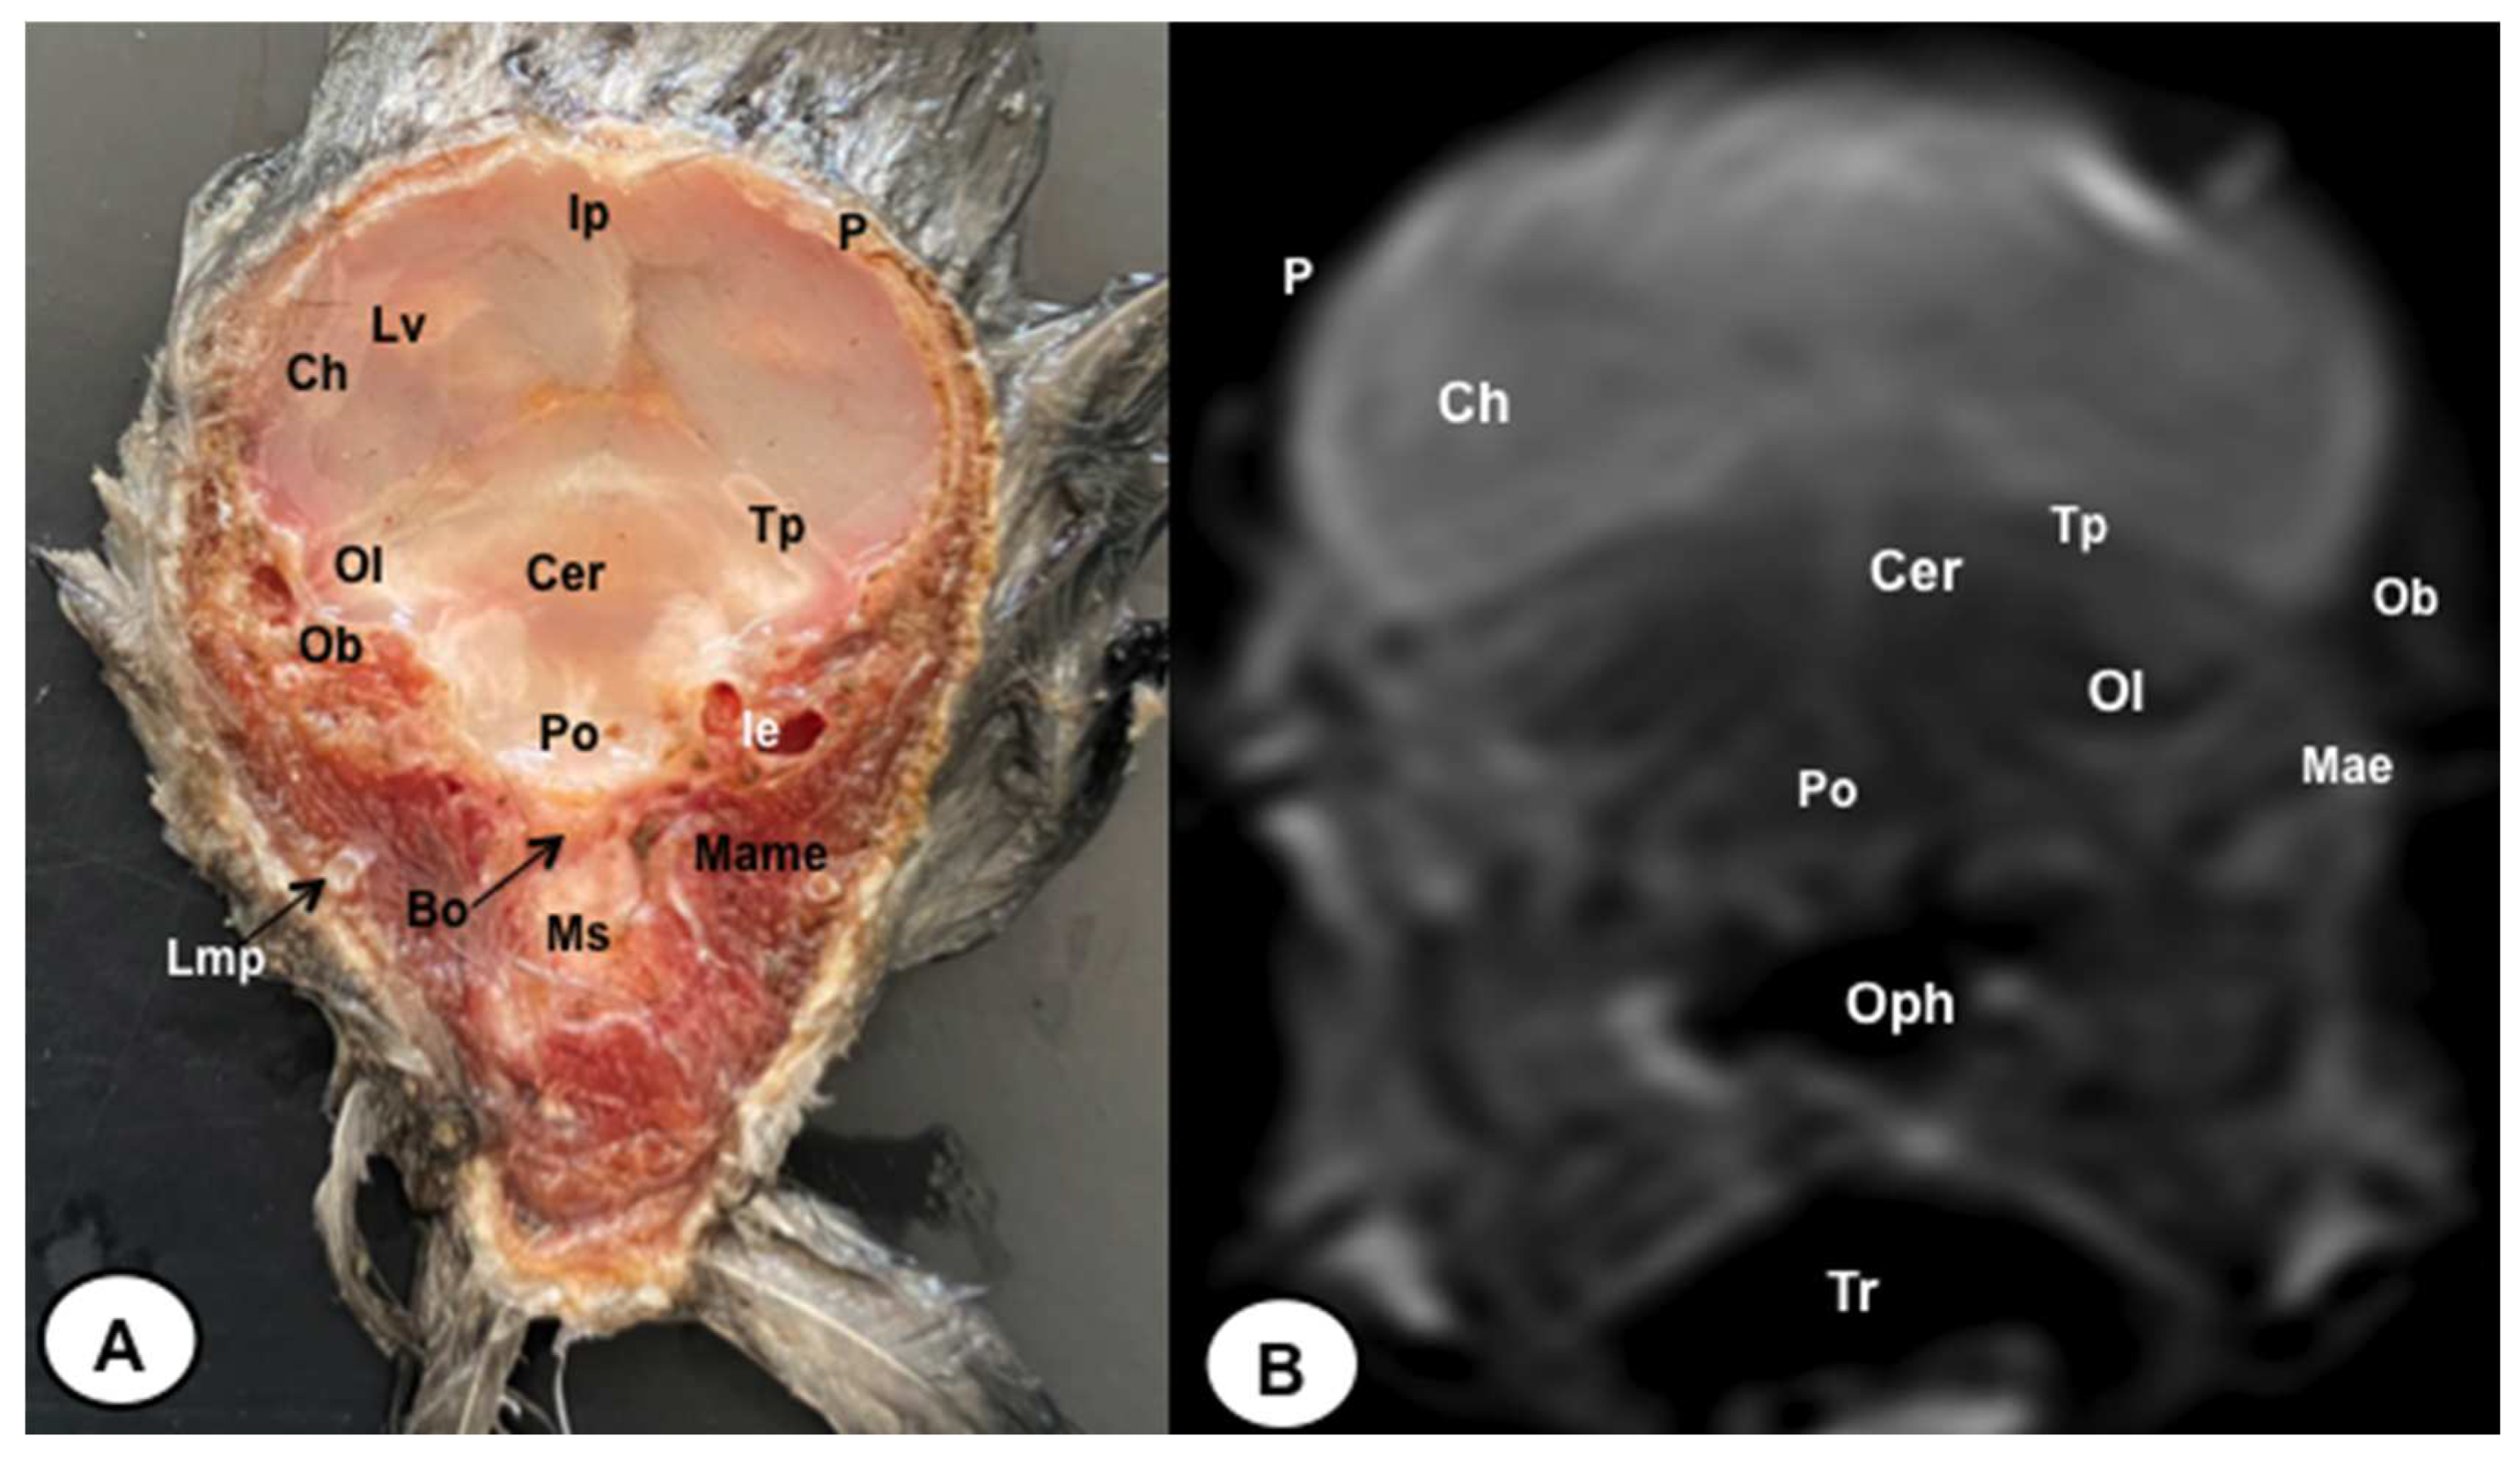

Figure 4. Transverse cross-section (A) and T2W MR (B) images of the atlantic puffin head at the level of the optic lobe corresponding to line III inFigure 1. P: Os parietale; Ip: interparietal bone; Lv: lateral ventricle; Tp: tentorial process; Bo: Os basioccipitale; Ob: otic bones; Ch: cerebral hemisphere; Ol: optic lobe; Cer: cerebellum (body); Po: pons; Ms: medulla spinalis; Mae: Meatus acusticus externus; Ie: inner ear; Lmp: Lateral mandibular process; Mame: Musculus adductor mandibulae externus; Oph: oropharynx; Tr: trachea.

The anatomical sections presented in this study were quite helpful in identifying different structures belonging to the central nervous system and its associated structures, which were labelled following the Nomina Anatomica Avium. Therefore, we observed the avian brain with the telencephalic hemispheres containing the lateral ventricles (see Figure 4A and Figure 7A). Both hemispheres were separated by the fissura longitudinalis cerebri (Figure 6A and Figure 7A). In addition, transverse cross sections were quite helpful in distinguishing a slightly caudolateral disposed rostral groove, the vallecula telencephali, which was presented on the dorsal surface of each hemisphere, as well as a little pointed olfactory bulb situated at the rostral end of each hemisphere (see Figure 2A, Figure 3A and Figure 7A). The diencephalon was identified as a rostral continuation to the mesencephalon and represents the rostral limit of the brain stem (Figure 10A). The dorsal and sagittal anatomical sections allowed the visualisation of some components of the hypothalamus, such as the optic chiasm and the optic nerve penetrating the sclera (see Figures 8A–10A). Besides, these sections allowed us the identification of other components of the Atlantic puffin brain, such as the dorsal part of the mesencephalon, as well as the large unpaired median corpus cerebelli, the internal medullary body with an internal white substance and the little paired cerebellar hemispheres (Figures 4A, 5A, 6A, 7A 8A, 9A and 10A). Moreover, these sections allowed the identification of the ventral part of the rhombencephalon, including the pons and the medulla oblongata, which did not present an obvious demarcation (see Figures 4A, 5A, 6A, 7A, 8A, 9A and 10A).

No discernible anatomical distinctions were evident in the examined juvenile puffins. T2-weighted magnetic resonance (T2W MR) images demonstrated a precise alignment with the cranial structures observed in the cadaveric cross sections, furnishing comprehensive insights into the central nervous system (CNS) and its associated structures. Consequently, various constituents of the puffin head’s CNS, the bulbus oculi, and their related elements were adequately differentiated. Thus, in the transverse and dorsal planes, the two telencephalic hemispheres were homogeneous, displaying regions of moderate and hypointense signals corresponding to the cerebral hemispheres and lateral ventricles, respectively (see Figures 3B, 4B, 5B, 6B, 7B and 10B). Notably, these two planes facilitated the identification of the olfactory bulb, which was a small rostrally tapering structure with moderate and homogeneous signal intensity (see Figures 2B, 3B and 7B). The hyperpallium, distinguished by its curved dorsal contour and moderate signal intensity, was another distinct structure identified (see Figure 3B). Conversely, the diencephalon, another forebrain component, displayed limited differentiation from the adjacent mesencephalon, manifesting moderate to low-intensity signals (see Figure 10B). Additionally, prominent features of the mesencephalon, such as the optic lobe, were exclusively discerned in the dorsal T2W MR images, showcasing analogous signal characteristics (see Figures 4B, 8B and 9B). Other essential components of the CNS, including the pons, and the medulla oblongata, were identifiable in the transverse, dorsal and sagittal planes, characterized by low-intensity signals (see Figures 4B, 5B, 6B, 8B, 9B and 10B). Adjacent to the brain stem, the corpus cerebelli and the small paired cerebellar hemispheres exhibited poorly defined regions of hypo-and moderate intense signal (see Figures 4B, 5B, 6B, 7B, 8B, 9B and 10B).

In relation to the mesencephalon, the optic lobes were discernible in both transverse and dorsal cross-sectional views, as well as in corresponding T2-weighted magnetic resonance (MR) images. These structures were situated in lateral proximity to the telencephalon, and their differentiation from the telencephalic hemispheres was evident due to the presence of the tentorial process, which resulted in a distinct demarcation between these regions. Notably, these lobes exhibited substantial volume, primarily attributed to their processing of a significant portion of visual information [46,61].